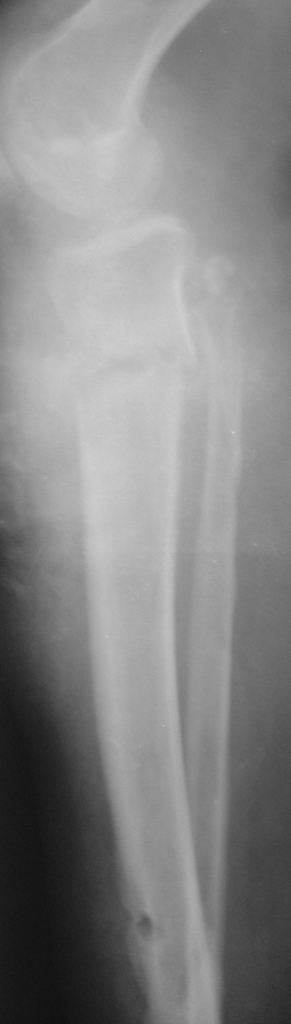

[Ortho] Патологический перелом голени, остеомиелит

Женщина 30 лет,инвалид 1-й группы по рассеяному энцефаломиелиту (клинически нижний парапарез). В январе 2008 года получила закрытый винтообразный перелом большеберцовой кости в н/з и шейки малоберцовой кости со смещением отломков. После травмы развились обширные эпидермальные пузыри голени и голеностопного сустава. После заживления ран произведено наложение аппарата Илизарова.П/о период без особенностей, больная поставлена на ноги (с ходьбой, естественно, проблемы). Наблюдалась на дому. Спустя месяц после операции отмечалось воспаление м/тканей области спиц проксимального базового кольца аппарата, отек в/з голени (больная передвигалась по дому на четвереньках!).Пришлось поменять кольцо на больший диаметр.Воспаление купировали. К концу второго месяца фиксации воспаление в области верхних спиц опять возникло, отделяемое сукровично-гнойное, незначительное.Проводилось местное лечение, отмечался умеренный отек голени в в/з, болезненность, гиперемии не было. Через три месяца после операции - клиническая проба, перелом сросся. Аппарат демонтирован. Спустя 4-5 дней после демонтажа отмечалась гипертермия до 39 в вечернее время. Раны кроме верхних зажили без проблем, верхние - в прежнем состоянии (незначительное серозное отделяемое).Проводилась АБТ, туалет ран, дренирование. Спустя 2 недели после снятия аппарата мать больной отметила появление подвижности в области коленного сустава. При осмотре - деформация голени в в/з (на уровне верхних спиц), подвижность на протяжении в/з, болезненность. Отек умеренный в в/з, гиперемии нет, гипертермия локальная умеренная.Коленный сустав отечен, жидкости нет. Сделали снимки (в приложении) - вот какая картина  Больную госпитализировали - гипсовая лонгета, противовоспалительная терапия, взяли посев из ран. В анализах -лейкоциты до 8 тыс, сдвига формулы нет, СОЭ 42, но больная проходит курсы лечения бетафероном по РЭМ.

Имя     : Сенина-прямая.JPG